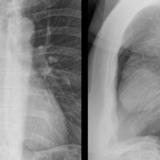

Case 2

Thymoma